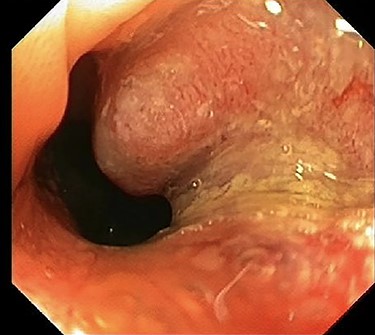

Colonoscopy revealed a polyp in the sigmoid colon and an obstructing tumor suspected for CRC (20 cm from the anal verge) (Fig. 1). An abdominal contrast-enhanced computed tomography showed four lesions in the liver suspected for metastases without lymphadenopathy (Fig. 2). Magnetic resonance of the liver showed five lesions suspected for metastases. Chest X-ray was normal.

Colonoscopy of the sigmoid colon revealing a polyp suspected for malignancy.